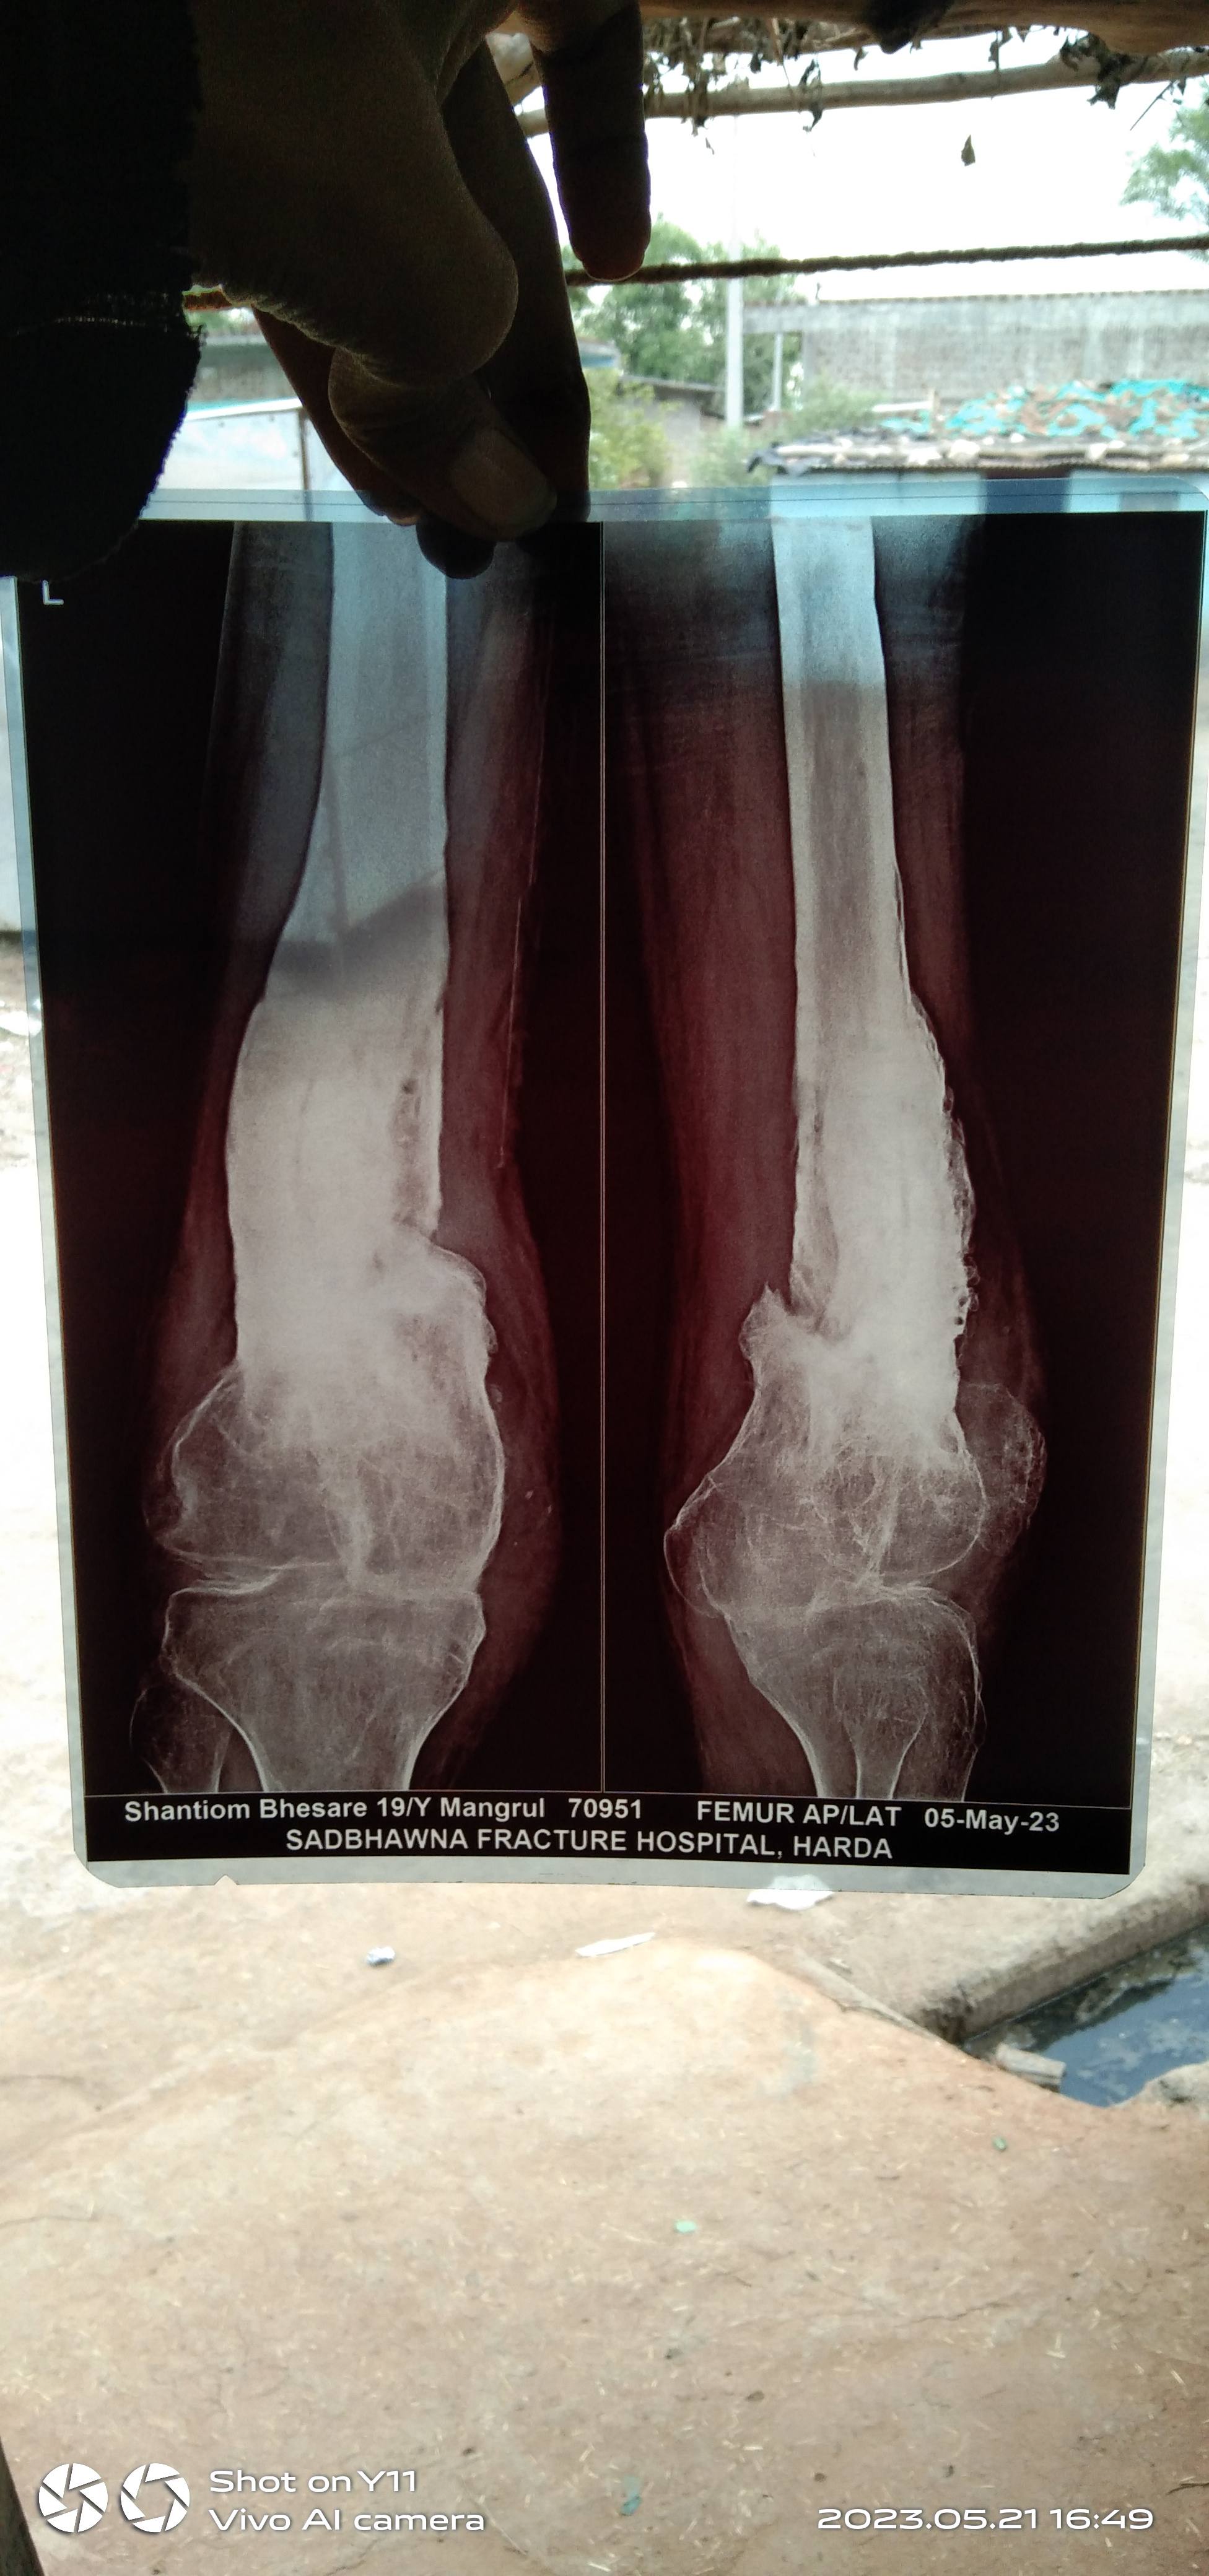

क्या ये मुख्यमंत्री आयुष्मान आरोग्य योजना में कवर है या पैड है कृपया रिप्लाई जरूर दीजियेगा। क्या इसके लिए गोल्ड नी इंप्लांट की नीड है